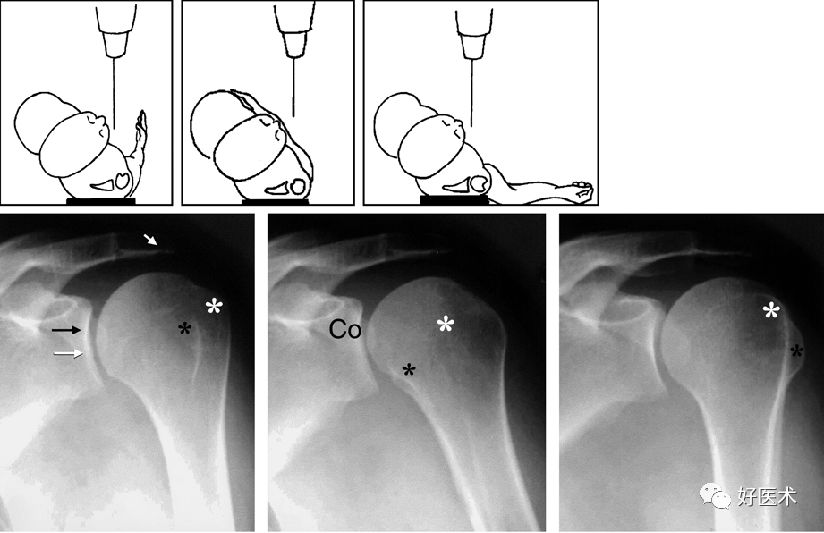

肩关节出口位

出口位X线检查使肩胛骨轴位显像。X线正切于“肩胛胸关节”,并且可对肩峰下间隙进行较好的评估

-

出口位X线片上,可见喙突、肩胛骨体部和肩峰成Y型,肱骨头位于Y型的中心

肩关节腋窝位

对关节盂的上部及后部、肩胛颈的正切显像

同时对盂肱关节位置关系、肩锁关节较精确的评估

肩关节顶斜位

对肱骨头的上后部分、肩关节关节盂前缘的下部很好的成像